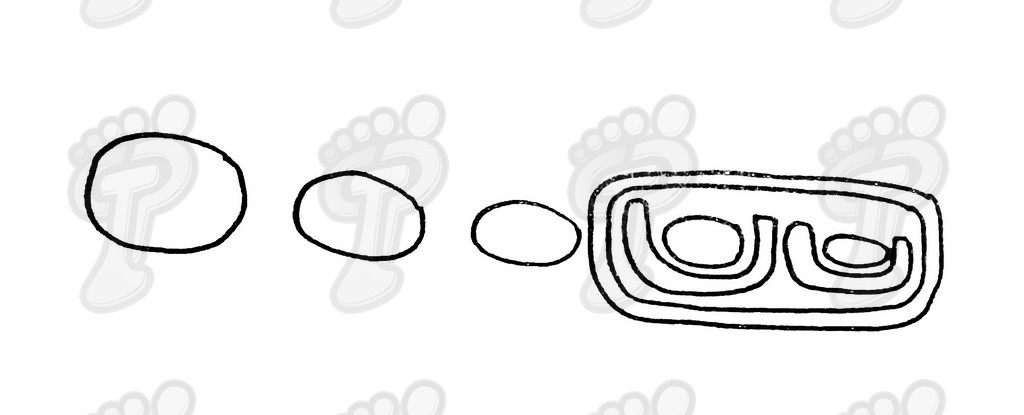

Denominamos exóstosis digital a la hipertrofia parcial circunscrita de la superficie de la falange de cualquier dedo. La exóstosis es una prolongación de la falange sin rotura del periostio y sin migración. Radiológicamente es unilateral, de configuración osteocartilaginosa, sin núcleo de osificación propio, radiopaca, y sin deferencia con el hueso adyacente. La exóstosis produce visualmente una hiperqueratosis distal o próxima a ésta, ya que entre la piel y la exóstosis no hay tejido suficiente para producir heloma. Las características de esta patología son:

Se realiza la técnica mediante anestesia troncular y sin hemostasia (o al menos, tras el legrado). Hacemos una incisión transversal en la zona dorsoplantar distal a dos o tres milímetros de la prominencia ósea, se introduce el bisturí perpendicularmente al eje de la falange hasta tocar hueso, y a partir de ahí, se desciende bien próximo al tejido ósea para separar partes blandas y delimitar la exóstosis. No se debe incidir lateralmente porque podríamos dañar el paquete neurovascular. Se introduce un cincel separando tejido óseo blando y se delimita la prominencia ósea, la cual suele ser mayor que en la radiografía debido a una zona cartilaginosa radiotransparente. Se legra exhaustivamente con la lima de proximal a distal y de profundidad a superficie (sin vaivén). En las primeras capas (cortical y periostio) notamos que la lima patina y a continuación percibimos el raspado óseo. Con el pulgar de la mano pasiva presionamos de proximal a distal para que salgan al exterior las partículas óseas legradas. Legramos ampliamente ya que al producir un traumatismo óseo siempre hay una regeneración ósea debida a la rica red capilar superficial. Si no lo hacemos así, se puede volver a regenerar el tejido óseo produciendo de nuevo y en poco tiempo la exóstosis. Favorecemos el sangrado de la zona para ayudar a eliminar posibles partículas óseas. Lavamos abundantemente la incisión con suero fisiológico. Volvemos a realizar otra radiografía dorsoplantar intraquirúrgica, a ser posible en la misma posición pre-quirúrgica (la radiografía oblícua no da imagen real del tamaño de exóstosis y la lateral no muestra nada). Hemos de observar en la radiografía que la cabeza de la falange proximal está en el mismo plano que la base de la falange media, ya que si no puede producir algias post-operatorias. Si observamos una nebulosa en la radiografía, son pequeñas partículas o fragmentos óseos que deben drenarse mediante lavados ya que si no se reagrupan y vuelven a regenerar la exóstosis de nuevo. Se han de hacer lavados y radiografías hasta quedar la zona totalmente limpia de fragmentos óseos. Infiltramos anestésico y corticoides en proporción 9 a 1. No hemos de abusar del corticoide porque al entrar en contacto con la trabécula ósea que hemos dejado como capa externa, puede producir problemas graves post-operatorios, tales como la osteoporosis. Se aconseja primero cargar el corticoide y luego el anestésico para evitar que se cristalice el corticoide produciendo trastornos yatrogénicos. Una vez infiltrada la mezcla, presionamos la herida proximal a distal para drenarla ya que sólo nos interesa el efecto farmacológico antiinflamatorio. A continuación, suturamos con seda 5/0 mediante dos puntos simples. En el caso que os mostramos ferulizamos el quinto dedo con una gasa de “U”, impidiendo así la movilización dorsoplantar y, para más sujeción, se une al cuarto dedo con la ayuda de un vendaje circular. Puede impregnarse en yodo la férula en forma de “U” para darle mayor rigidez o consistencia y por lo tanto, menor movilidad al quinto dedo. El vendaje debe ser semicompresivo alineado el dedo. Aconsejamos al paciente reposo durante 48 horas. Pautamos la analgesia correspondiente, y le informamos de las actuaciones que debe efectuar ante determinadas anomalías. Retiramos el apósito quirúrgico a las 48 horas y se cura con povidona yodada dos veces al día (mañana y tarde). Enseñamos al paciente a hacer el vendaje en forma de “U”. A los siete días retiramos la sutura y confeccionamos una cresta de silicona, que debería emplear hasta alcanzar la normalidad articular. Dicha silicona ha de ser utilizada durante un período que oscile entre seis meses a un año.